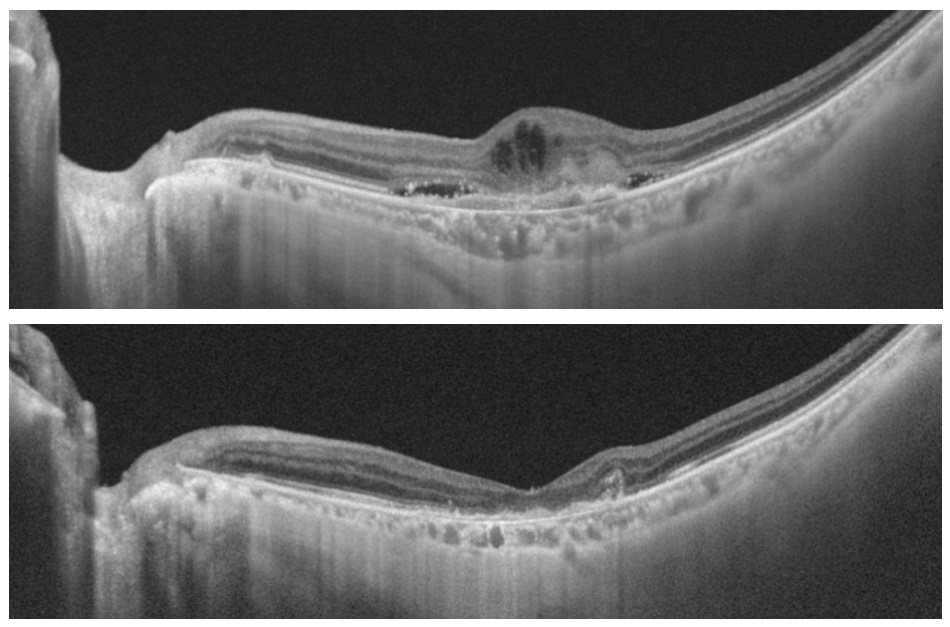

図2:滲出型加齢黄斑変性に対する抗血管内皮増殖因子(VEGF)剤による治療

光干渉断層計(OCT)で治療前にみられた網膜の浮腫(上図)が治療後には消失しています(下図)